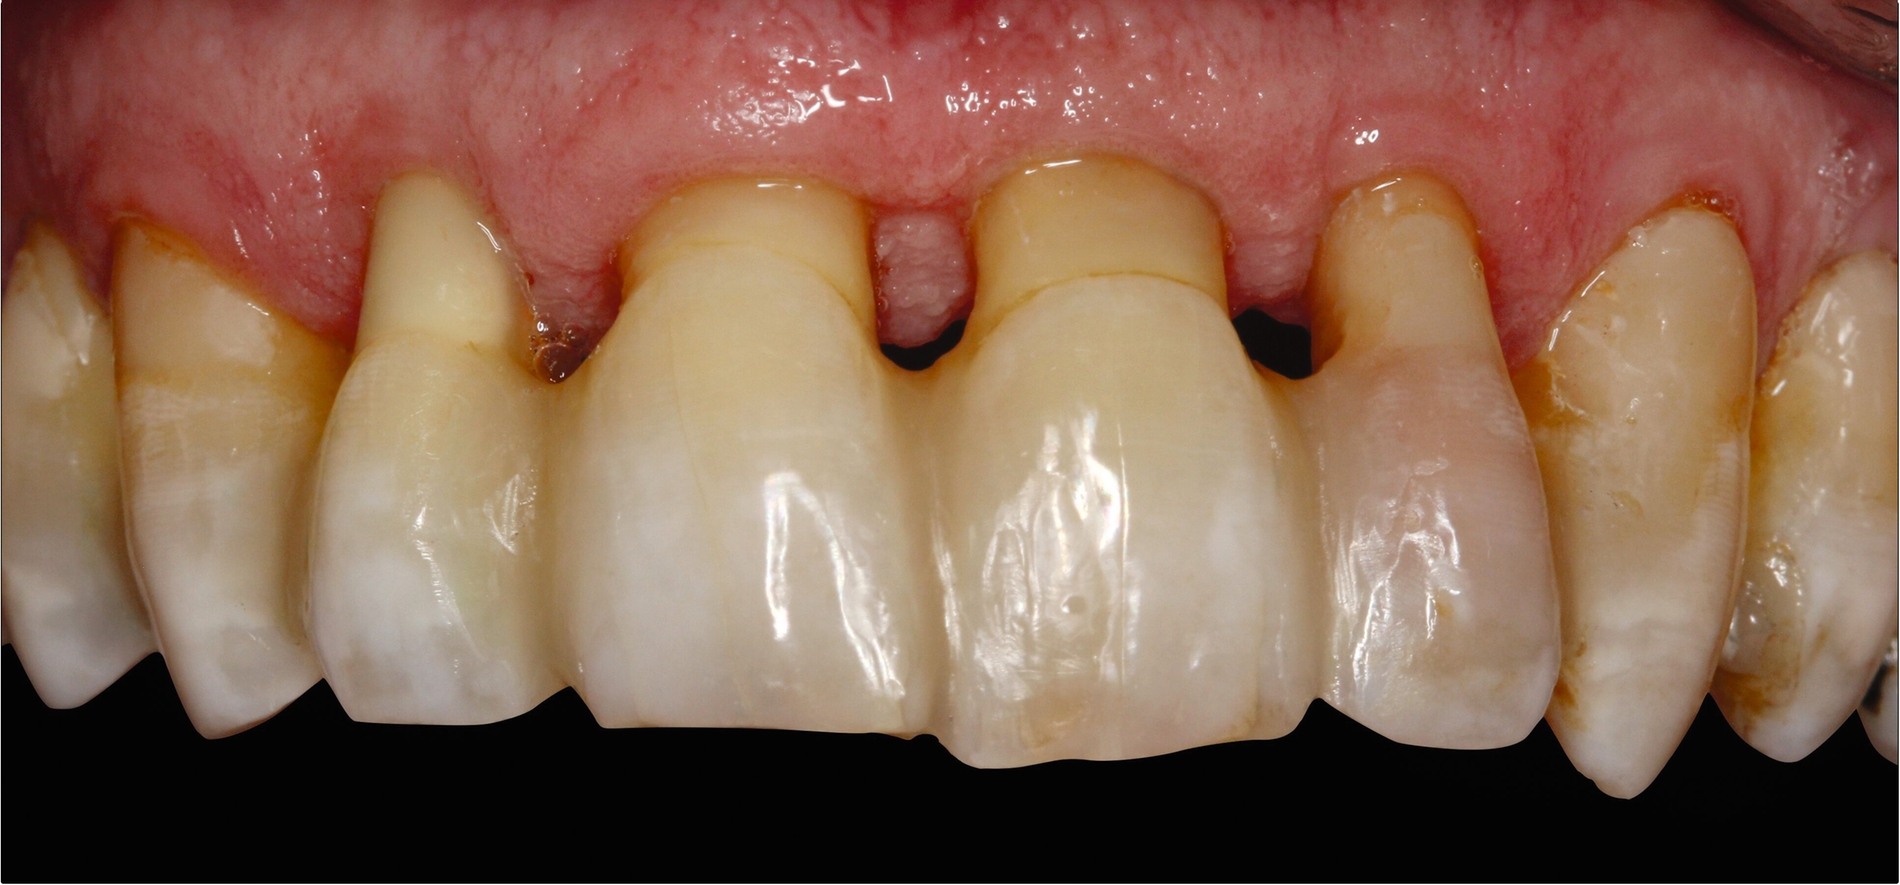

Es gibt viele Möglichkeiten, permanente Schienungen von Zähnen mit Komposit alleine oder in Kombination mit Glasfasern durchzuführen. Die Verblockung der Approximalräume benachbarter karies- und füllungsfreier Zähne mit Komposit stellt eine ästhetisch akzeptable Schienung dar und kann so vorgenommen werden, dass die parodontale Reinigungsfähigkeit erhalten bleibt (Abbildung 5). Als Nachteil dieser rigiden Schienungsform sind mögliche Schienungsfrakturen zu nennen, die insbesondere bei höheren Mobilitätsgraden vorkommen. Glasfaser-Komposit-Schienungen weisen ebenfalls eine hohe Rigidität auf. Sie können zahnhartsubstanzschonend an den oralen Flächen der Zähne angebracht werden. Alternativ kann bei gut ausgeformten Zahnbögen im Frontzahngebiet eine inzisale Schienung vorgenommen werden. Dafür ist zumeist eine Präparation erforderlich, um Platz für das Schienungsmaterial zu schaffen. Bei approximalen Füllungen oder bei Karies an angrenzenden Flächen benachbarter Zähne können auch zwei Approximalfüllungen miteinander verbunden werden, um eine Schienung durchzuführen.